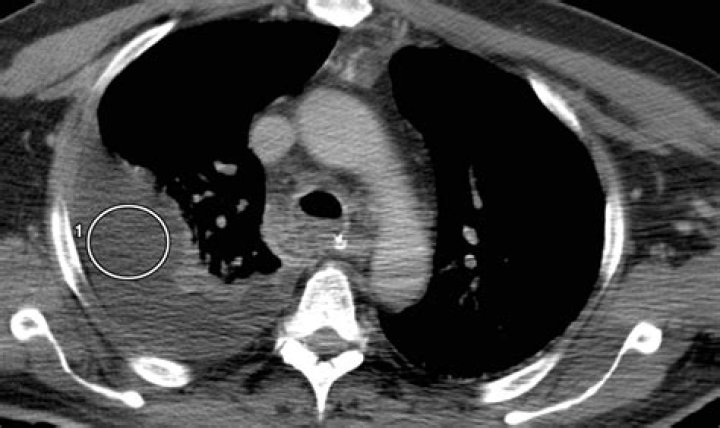

Thoracentesis and pleural fluid analysis are the criterion standards to establish a diagnosis of chylothorax. Alternatively, in a postsurgical patient, tube thoracostomy output can be analyzed. Pleural fluid analysis for triglyceride content helps to confirm the diagnosis of chylothorax.

Chylothorax is a rare condition that results from thoracic duct damage with chyle leakage from the lymphatic system into the pleural space, usually on the right side. It has multiple aetiologies and is usually discovered after it manifests itself as a pleural effusion.

Chylothorax is characterised by the accumulation of chyle, a lipid and protein rich fluid within the pleural space. It often occurs due to thoracic duct trauma which can be caused by increased pressures. On Koala, this postoperative complication is often seen post cardiac surgery in patients with redivac drains insitu.